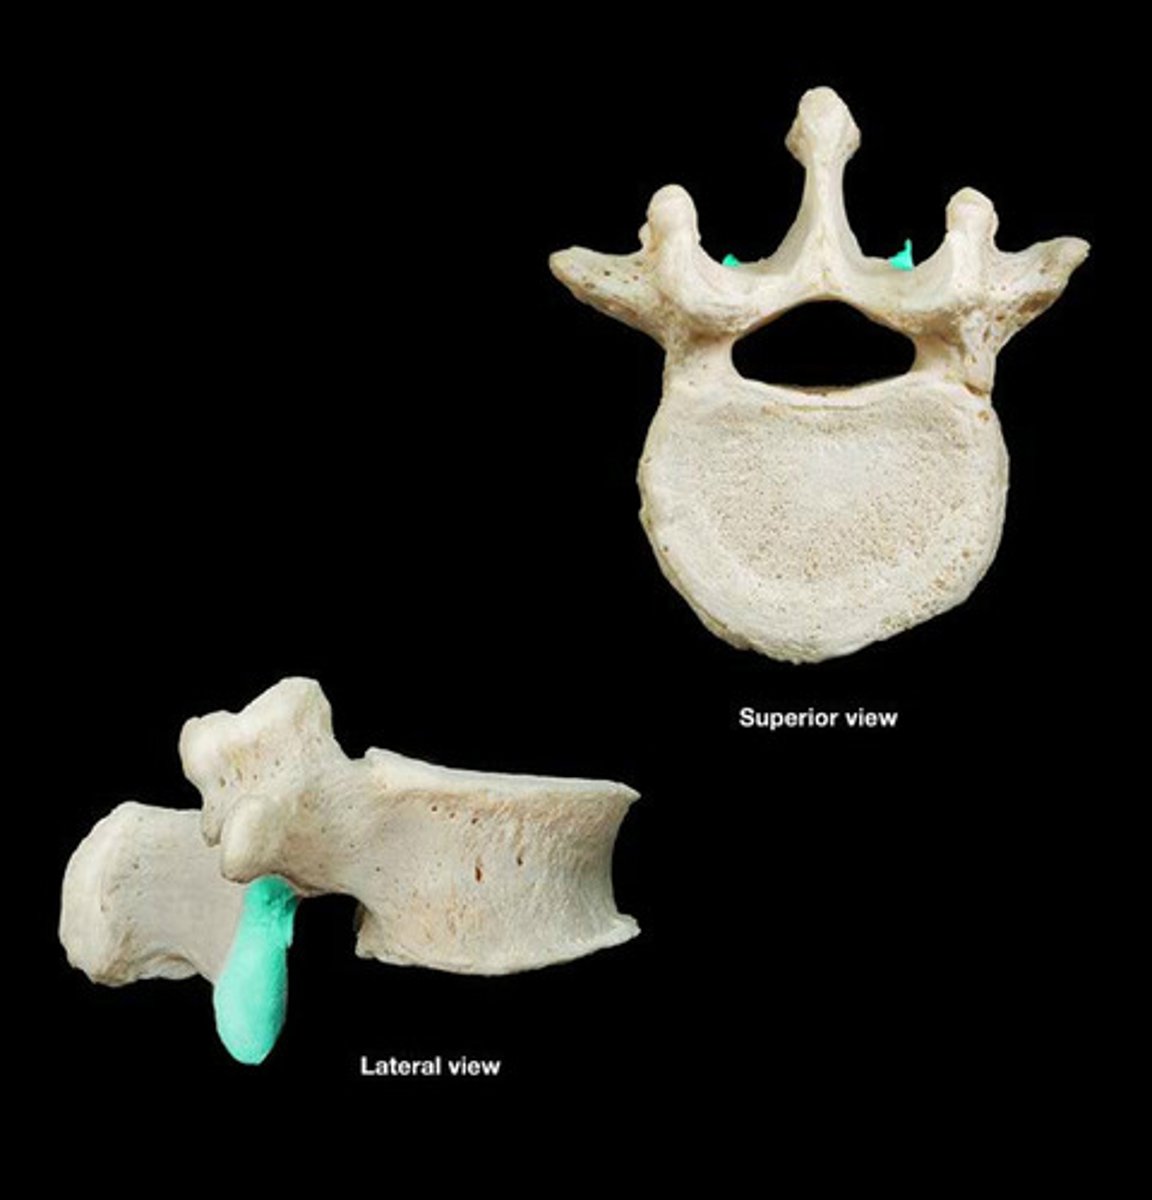

Lumbar Vertebrae 5

Vertebral Body

Superior Articular Facets

Inferior Articular Facet